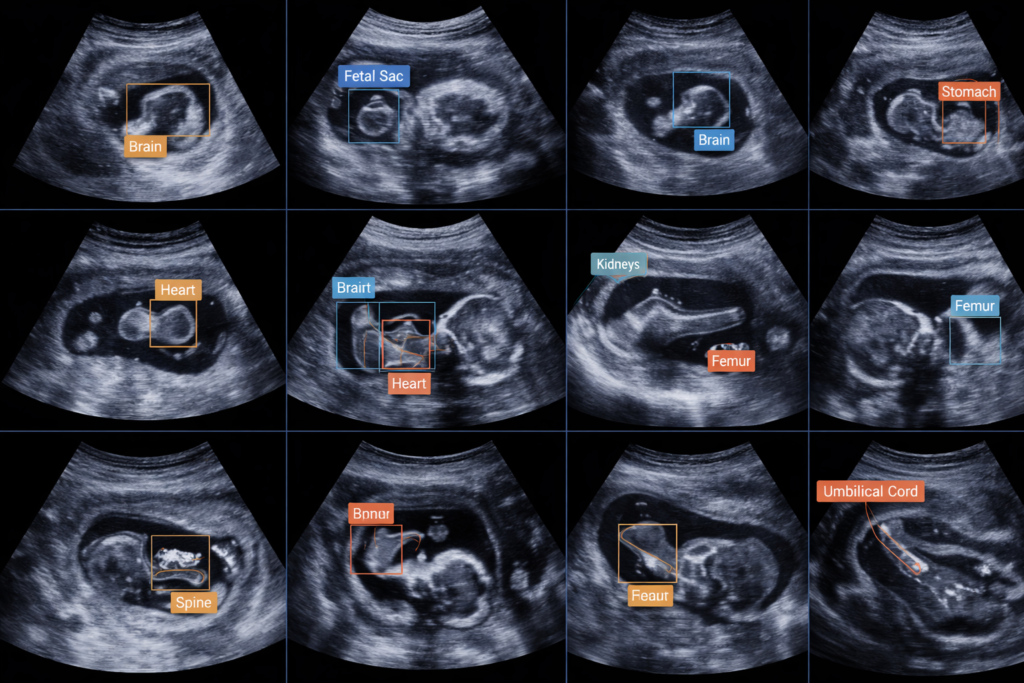

40,000+ Ultrasound Frames Annotated for Fetal Abnormality Detection

The client is a healthcare AI innovator developing a cloud-based prenatal screening platform used by radiologists and obstetricians to detect fetal abnormalities from ultrasound imaging. Their product aimed to support early-stage detection of congenital disorders across diverse hospital environments.

Organ-level pixel segmentation for:

Brain & skull

Spine & vertebrae

Abdomen & femur

Heart chambers

Bounding box tagging for anomaly-prone zones

Temporal frame-by-frame abnormality labeling for ultrasound video clips